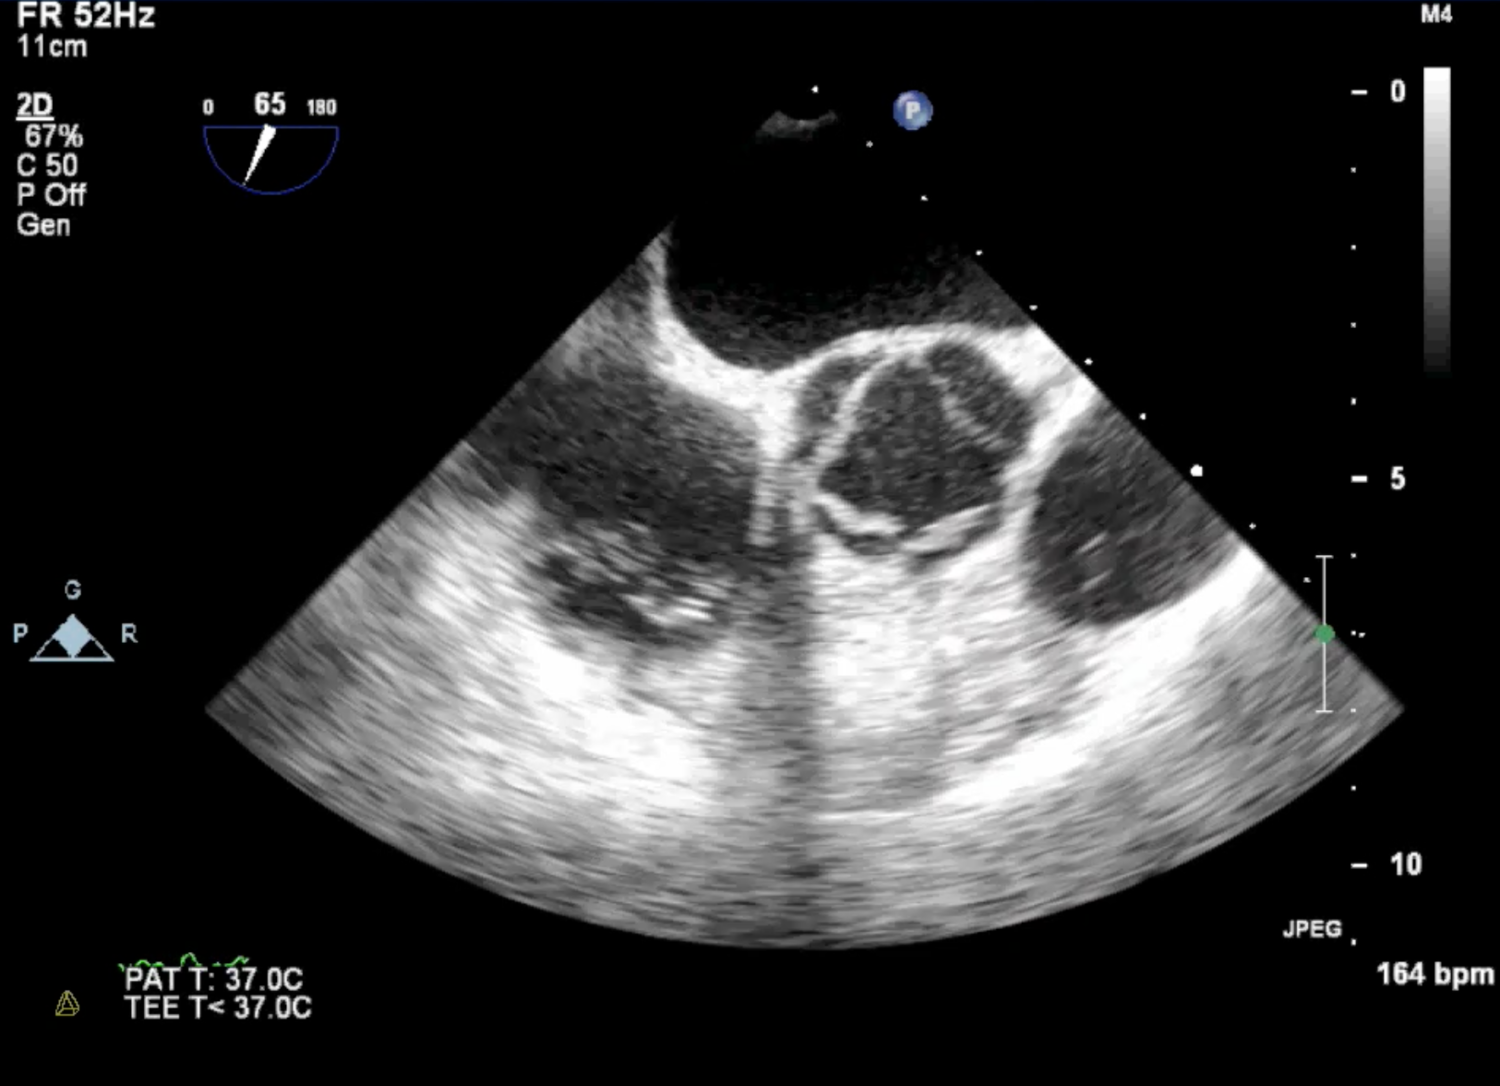

Trans-oesophageal echocardiograms

More detail images of the heart can be achieved using a trans-oesophageal echo probe. This entails the patient swallowing a fine probe (usually after receiving intra-venous sedation) which then sits in the oesophagus while images are recorded. In this case an unusual abnormality of the aortic valve is seen.